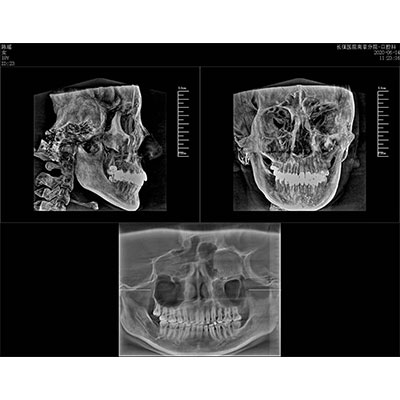

该款牙科CBCT产品采用动态平板探测器,获得三维图像的同时还具有数字化全景功能,广泛应用于口腔颌面外科、正畸科、正颌外科、种植科、牙体科、颞下颌关节科等术前术后。

专有三维重建算法,可提供任意位置高清断层影像。

通过三维容积影像,提取高清口腔全景影像。

专有图像校正技术,去除金属伪影,提高图像分辨率。

可同时观察轴向面、冠状面和矢状面图像,方便临床诊断。